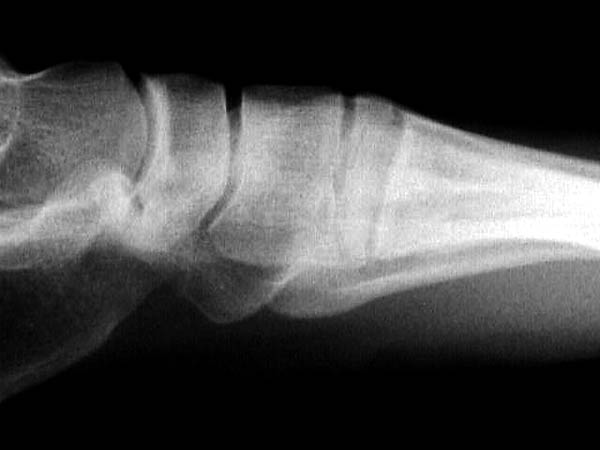

Здесь КТ и сравнительные снимки стопы под нагрузкой.

Диагностировано повреждение медиальной и латеральной колонны.